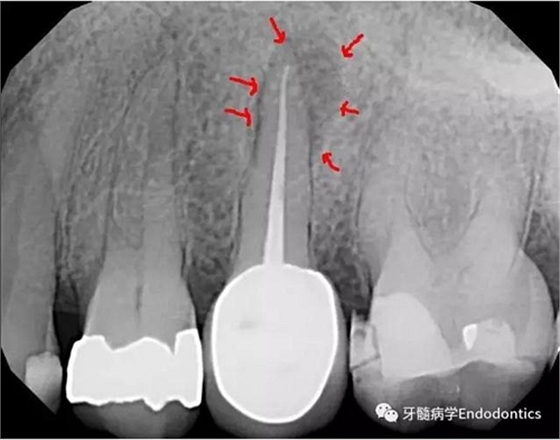

圖1.術(shù)前X線片示#25根管治療完善,根尖周圍大面積病變